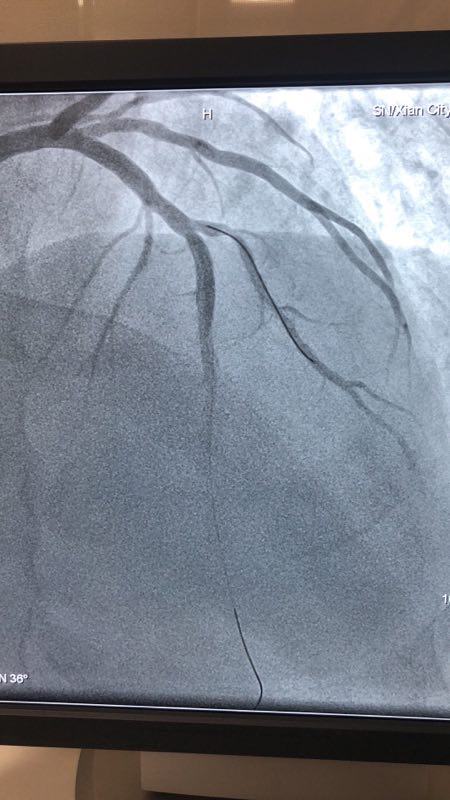

2018年12月27日下午,男同视频 CCU病区成功应用药物涂层球囊扩张术救治一名支架内再狭窄患者。

此例患者,男性,56岁,11年前因心绞痛在西京医院行冠状动脉造影检查后于D1对角支置入1枚支架治疗。术后患者口服“阿司匹林肠溶片、氯吡格雷、阿托伐他汀”等药物治疗1年后自行停药,并有长期大量吸烟史。2018年12月24日患者突发胸痛、胸闷,急来男同视频 就诊。急诊行冠状动脉造影检查提示D1对角支原支架内再狭窄70%-90%。急救中心主任张誉洋副主任医师考虑到第一对角支管径较小,于原支架内再次置入支架引起再狭窄的风险极大,遂建议应用药物涂层球囊扩张术治疗D1对角支原支架内狭窄。与患者充分沟通后,于12月27日行冠脉药物涂层球囊PTCA术治疗,造影显示血管开通情况良好,术后患者症状明显改善。

冠脉药物涂层球囊扩张术,由于不需置入外来物质,因此可以避免置入支架的很多缺陷。既达到“支架”扩张血管的目的,同时还能避免术后血管再狭窄,可谓一举两得。该技术可应用于小血管病变和不能耐受长期强化抗血栓治疗的患者,随着临床应用的增加可为更多患者带来福音。